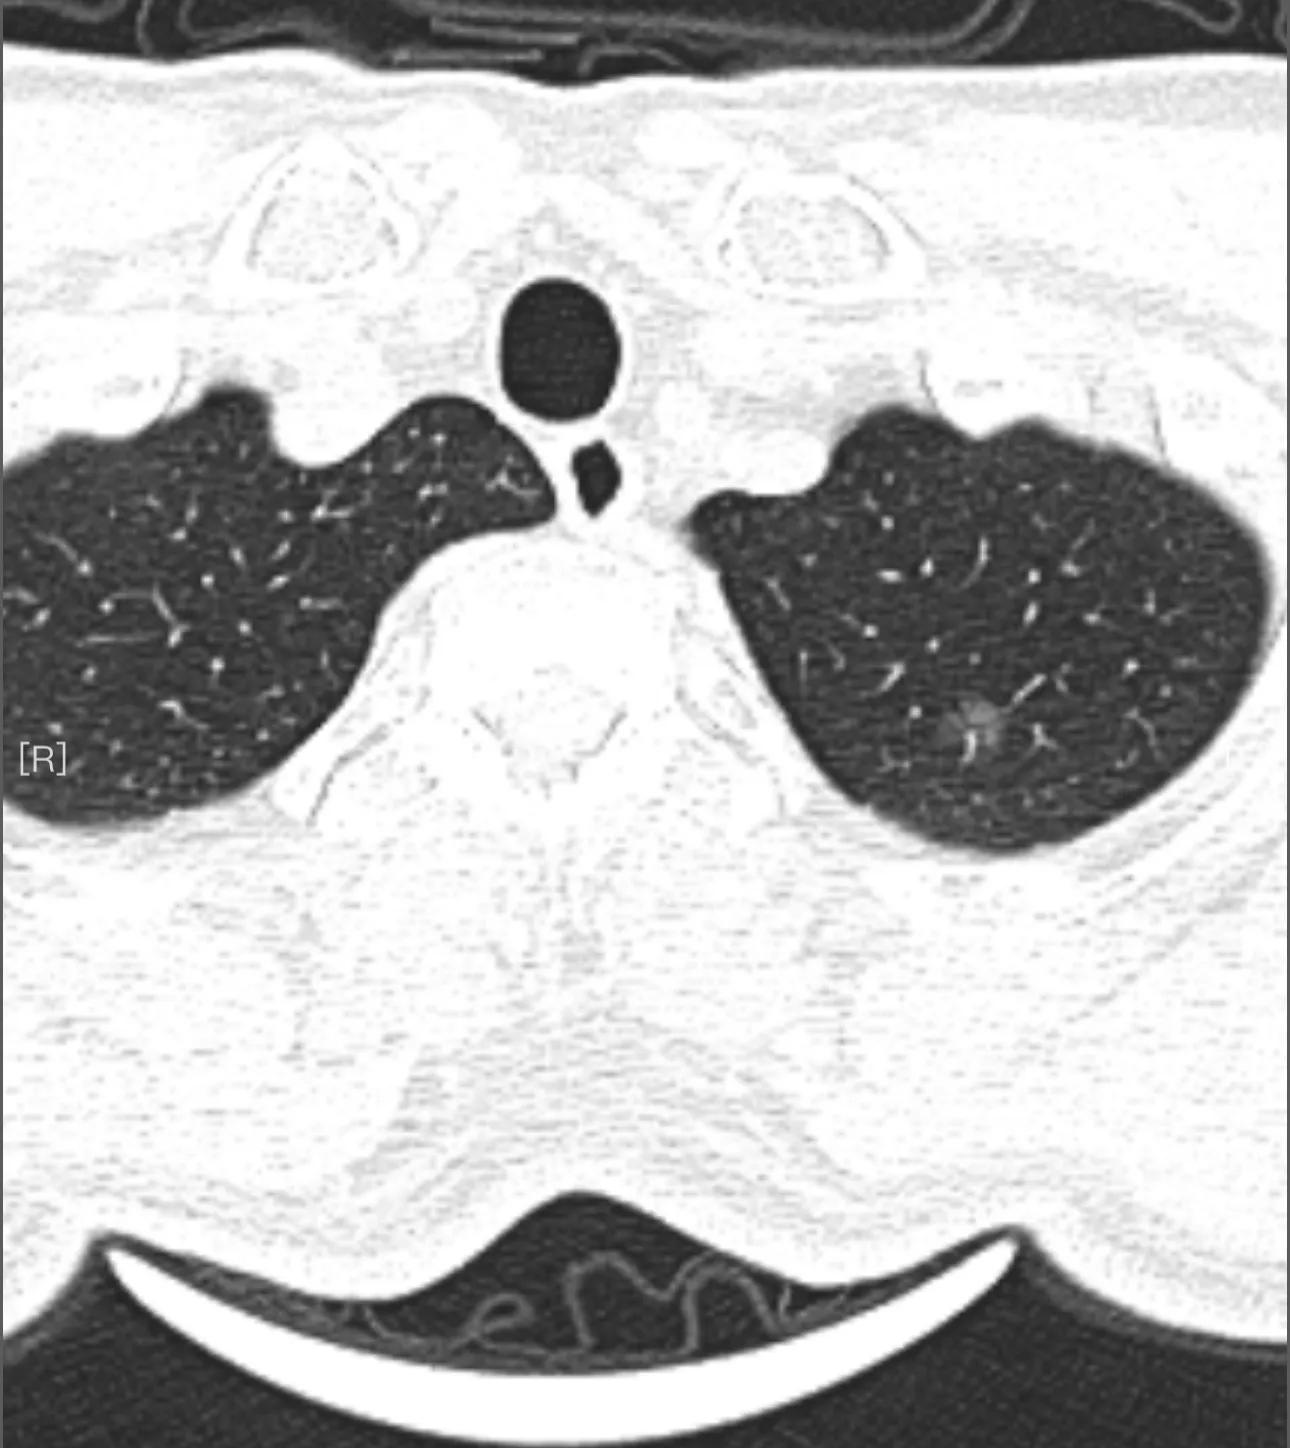

坐在上海返回西安的高铁上,我的思绪犹如这飞驰的火车一样,也回到了2020年的七月。一次意外的胸部CT检查,查出了我的双肺里长了三个肺磨玻璃结节,谁都知道肺磨玻璃结节意味着什么……,当时的报告单上写着三个结节中最大的结节直径约5mm左右,我于是百度了一下,小于5mm大多都是良性,所以在焦虑了几周后也就不太焦虑了!接下来的日子就是当在抖音里刷到肺结节内容时,听到肺结节是早期肺癌时心里会焦虑一次,然后又告戒自己你是5mm的,是良性的!就这样在轻度焦虑中过了两年半,只是在每次复查CT时前几天都吃不好睡不着!现在想想这肺结节还真是折磨人呀!

对我来说真正的恶梦才开始,时间来到了2023年2月23日,在经历了几天的极度焦虑后,(为什说是极度焦虑呢?因为是我看到了肺结节在外科切除手术治疗时,要插管,全麻,切除肺叶或肺段等肺组织,所以震惊到了我,所以才会极度焦虑,害怕这次检查有什么变化!),我来到医院进行肺结节复查,真是怕什么来什么!这次报告第一条就是左肺尖发现一枚直径约9mm的磨玻璃结节……怎么会?我的第一反应是这不可能!得到的答复是之前也许密度浅,没发现……好牵强的解释呀!之后,我拷贝了CT影像,复制了U盘,就去了西安几家排名前几的医院,有的说做手术切掉,有的说随访!我又开始焦虑了,这次是很焦虑,因为一想到做外科手术切掉肺结节,我就极度焦虑,而且是恐惧到极点!